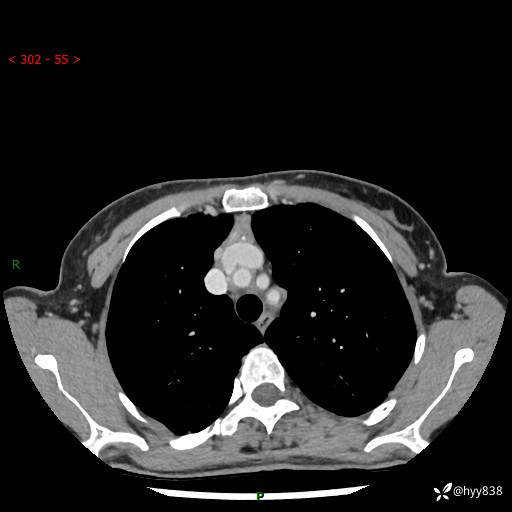

增强动脉期+静脉期